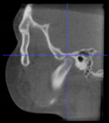

Three points determined the Acta plane: O, F right (FR), and F left (FL) (Table 2). Point O is the midpoint between the most craniodorsal point of the dorsum Sella and the most posterior dorsal point of the Basion in the midsagittal plane (Figure 1). Both points F are a result of the intersection between two lines: the line that connects the most inferior points of the lower orbital margins, right and left, and a line perpendicular to this line that runs through the most external points of the orbital margins, right and left (Figure 2). The new transverse reference plane, the Acta plane (Figure 2), is created by connecting the O-point (Figure 1) with FR and FL (Figure 2).

Figure 1.

Point O (green dot) is the midpoint between the dorsum Sella (Se) (red dot) and the Basion point (Ba) (yellow dot).

When determining the internal reference of the skull, the aim was to determine an origin point in the midsagittal plane, as previous studies have confirmed the consistency of the landmarks in the midsagittal plane [17,34]. At first, the midpoint between the left and right anterior clinoid processes was considered as the origin point. However, the left and right anterior clinoid processes have been reported as a reference with low reliability [35], and they were asymmetric in dry skulls as well as in many CBCT images from this sample. The second option was to use the most anterior border of the dorsum Sella. However, the Sella landmarks (Sella, Sella inferior, Sella posterior) are highly dependent on the DICOM orientation [17,35,36]. On the other hand, the most superior-posterior point of the dorsum Sella seemed more accessible and less orientation-dependent on the CBCT images. However, after using this point to align the CBCT scans, the final head position rolled too far backward. This issue was probably caused by the excessively high position of the dorsum Sella relative to the F-points. To address this discrepancy, the origin point was set in a lower position. One of the options considered was the Basion point. However, its position was too low in regard to the F points, which resulted in a forward-rolled skull after reorientation. As a result, the midpoint between the Basion and the dorsum Sella was adopted as the origin point, named point O.